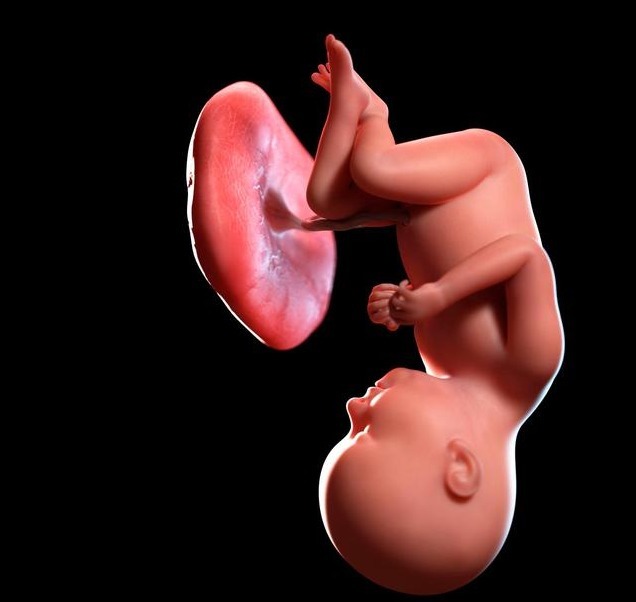

2.胎动孕37周后,不管胎儿有无入盆,由于宫内狭窄空间的限制,胎动幅度和频率都会有所减少,但是孕妇仍然可以根据胎动,检测胎儿的宫内情况。当胎儿的生命受到威胁时,胎儿会出现异常的胎动。这些异常的胎动,不仅表现在次数上,还体现在性质上。比如强烈的、持续不停的推扭样胎动或者踢动,以及微弱的胎动,都是不祥之兆。孕37周后,即使胎儿还没有入盆,但是胎位基本已经固定了。正常来说,此时的胎动多发生在小腹的中上部,很少出现在小腹下部。如果小腹下部经常出现胎动,很可能是胎位不正引起的,比如臀位和横位,一旦出现很容易造成分娩困难,也应该及时就医。3.假性宫缩孕37周后,子宫肌肉越来越敏感,假性宫缩也越来越频繁,不过这些假性宫缩的持续时间短,力量弱,不规律,不会让宫口打开,也不会引起分娩,所以孕妇不需要太担心。